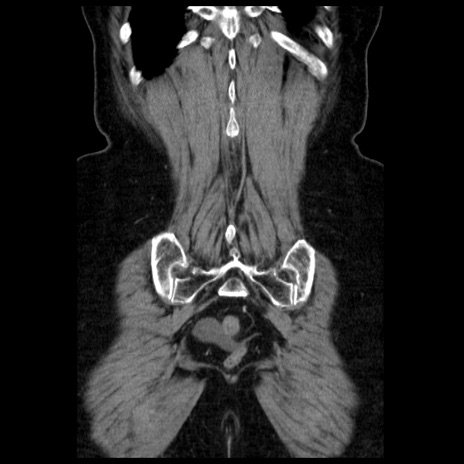

症例13(冠状断像)

【症例】70歳代女性

【主訴】腹痛、嘔吐

【現病歴】15時間程前(昨晩)より腹痛あり。今朝になっても症状の改善なく、嘔吐あり。腹痛も増悪あり、救急外来受診。

【既往歴】子宮癌全摘術後

【身体所見】意識清明、BP 121/72mmHg、P 74bpm、SpO2 100%(RA)、腹部:平坦・軟、腸雑音ほぼ聴取せず。下腹部・心窩部・臍左上に圧痛あり。反跳痛なし。

【データ】WBC 10600、CRP 0.15